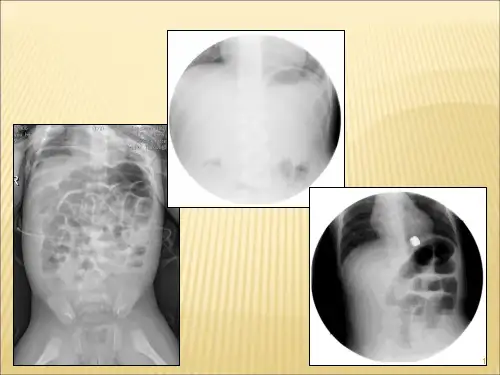

肠套叠空气灌肠复位技巧及注意事项医学PPT